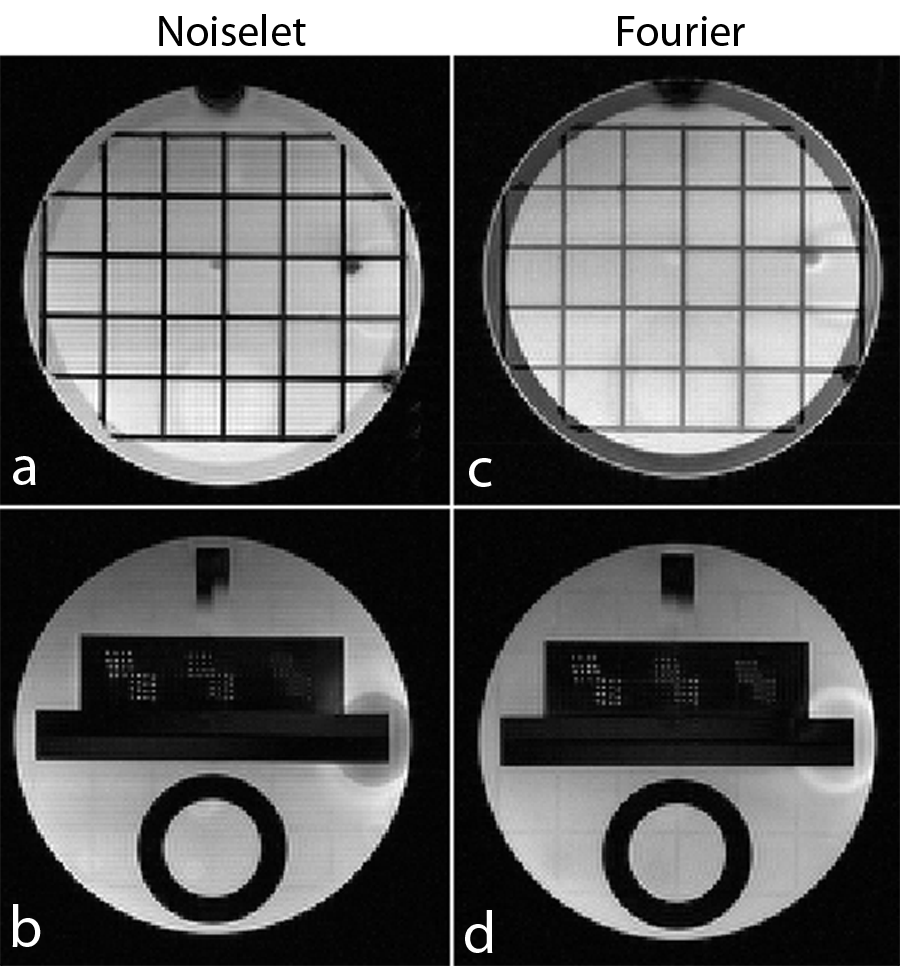

Non-Fourier encoding in general is sensitive to field inhomogeneities, but careful design of the sequence and good shimming can result in high quality images. To reconstruct the noiselet encoded data the inverse Fourier transform was taken along the frequency encoding axis and the inverse noiselet transform was taken along the PE axis. To reconstruct the Fourier encoded data, an inverse Fourier transform was taken along both axes. Fig. 11 shows the images reconstructed from the noiselet encoded data and Fourier encoded data sets. These images demonstrate that the noiselet encoding reconstructions are practically feasible and produce artifact free images. Fig. 11(c) shows a zoomed portion of the noiselet encoded image, while Fig. 11(f) shows a zoomed portion of the Fourier encoded image. The zoomed images reveal that the resolution of the image from noiselet encoding with 256 noiselet excitation is the same as that of the image from Fourier encoding with 256 phase encodes. Fig. 11 (g) and (i) show the T2 weighted images for the brain with noiselet encoding and Fourier encoding, respectively. Fig. 11 (h) and (j) show the T1 weighted images for the brain with noiselet encoding and Fourier encoding, respectively. It is evident from the in vivo images that the proposed noiselet encoding is feasible in practice.

Fig. 14 shows the images reconstructed with noiselet and Fourier encodings using 3D GRE sequence. In our implementation of noiselet encoding in 2D spin echo sequence, the flip angle of 10∘ was used, which results in loss of some available SNR. Therefore, we have implemented noiselet encoding in 3D Gradient Echo (GRE) sequence as shown in Fig. 1 (b), which uses noiselets encoding in one direction and Fourier encoding in other two directions. The noiselet encoding is performed using specially selective RF excitation pulse, while the Fourier encoding is performed using gradients. Phantom data was acquired using this sequence with the following parameters: FOV = 200200 mm2, TE/TR = 6.5/13 ms, slices = 32, FOV of slice = 160 mm, flip angle = 5∘ and (noiselets) phase encodes = 256. A 3D Fourier encoded data was also acquired with exactly same parameters. It can be seen from the images that the noiselet encoding provides similar quality of images to that of Fourier encoding. These images are only shown here to demonstrate the feasibility that noiselet encoding can be implemented in 3D GRE sequence.